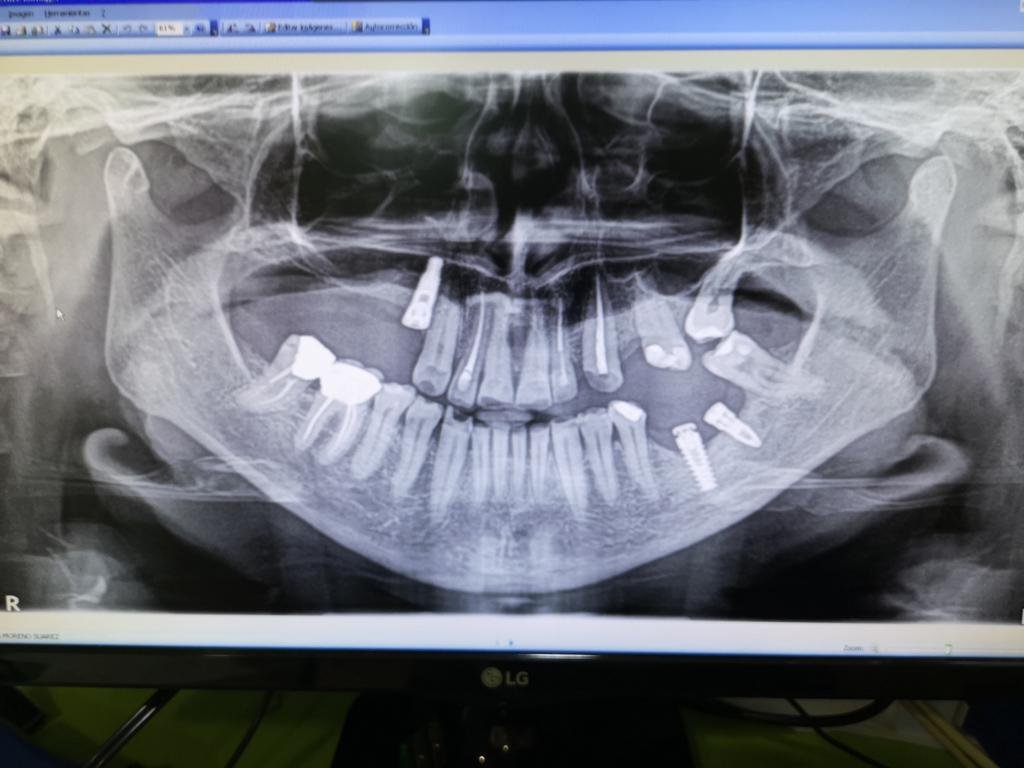

Hola , subo un caso que nos llega de otra consulta con dos prótesis híbridas superior e inferior sobre unos implantes que según le han dicho en su clinica son [...]